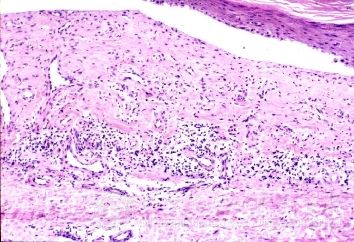

硬下疳是生殖器梅毒螺旋体较初侵入之处,并在此繁殖所致。典型的生殖器梅毒初期症状硬下疳为一减少痛苦性红色硬结,触之硬如软骨样,基底清洁,表面糜烂覆以少许渗液或薄痂,边缘整齐.损害数目大都为单个,亦可为多个。好发生于外生殖器。